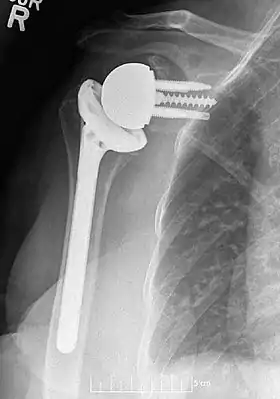

Plain film radiograph in anteroposterior (AP) view of a right shoulder status post reverse shoulder arthroplasty using a prosthesis with a lateralized center of rotation.

Plain film radiographs in anteroposterior (AP) view of left shoulders that are status post reverse shoulder arthroplasty using three design iterations each with a 135-degree neck-shaft angle and lateralized center of rotation.